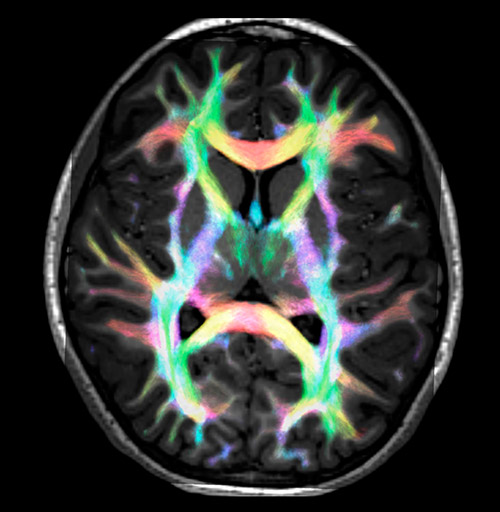

DEC TDI

UVM research fiber tracking density

Super-resolution directionally encoded color track-density imaging overlaid on T1-weighted structural MRI.

Super-resolution directionally encoded color track-density imaging

UVM research fiber super resolution

UVM research fiber tracking

UVM research super resolution